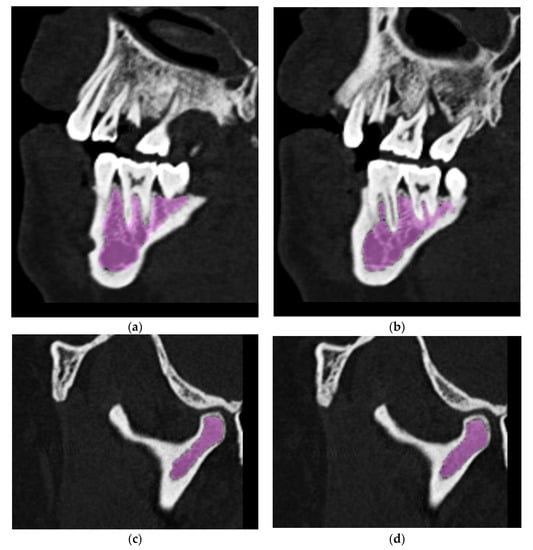

- Creation of an accurate model of the mandible together with the temporomandibular joint. The main assumption was to create a model that could be used for numerical analyses of various clinical cases, allowing the simulation of the work of fixing elements, assessment of the strength and durability of the fixation, and at the same time, without unnecessary simplifications, reflect real human anatomy. The input data were DICOM images obtained from medical imaging using computed tomography. Obtaining three-dimensional models of individual anatomical structures required the segmentation of tomographic images and then edition of the generated surface objects. Reverse engineering software for free modeling and a CAD program for parametric modeling were used.

2.2. Generation of a Three-Dimensional Model of Selected Anatomical Structures

2.3. Edition of STL Models